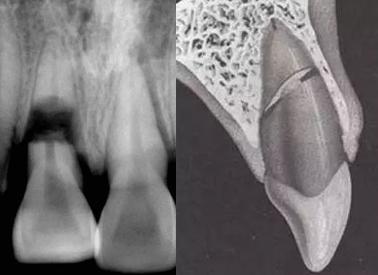

牙根折断X线片及示意图: